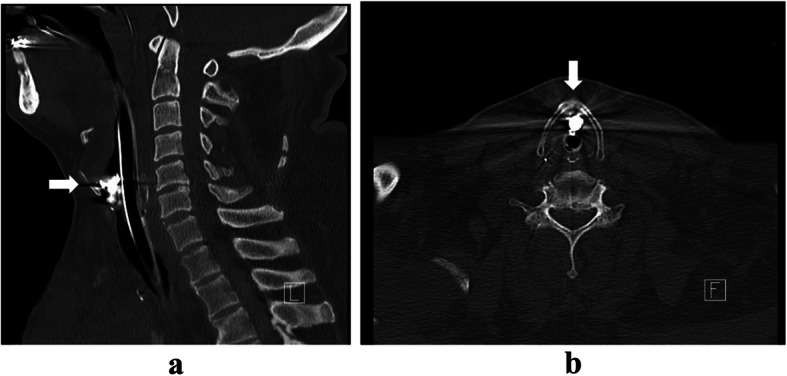

A chest X-ray on POD 34 revealed an abnormal shadow near the larynx (Fig. 1). Review of previous X-ray showed the same shadow in the hypopharynx on POD 19, although it was not identified immediately after arrival in the ICU. A loss of a front tooth was found on POD 22; however, a foreign substance was not confirmed in the oral cavity or on the abdominal X-ray, and the patient was placed under observation. A simple computed tomography (CT) scan on POD 34 showed a shadow with metal artifacts, indicating a crown bridge, outside of the tracheal tube, inside the trachea, and just under the glottis (Fig. 2). Upper esophageal gastrointestinal endoscopy performed on POD 34 also revealed tooth fragments in the stomach. The pharynx and larynx were examined at bedside using McGRATHTMMAC video laryngoscope (Medtronic, MN, USA); however, no foreign matter was found. Observation from the inside of the tracheal tube using the bronchial fiber revealed a foreign body in the trachea just below the glottis, outside (ventral side) the tracheal tube. We therefore considered that the removal of the foreign body in a well-equipped environment would be more suitable than in the ICU and that the foreign body would not cause airway obstruction immediately.

Fig. 2.

Simple CT scans on POD 34. a Sagittal section. An airway foreign body (arrow) was found on the ventral side of the tracheal tube at the level of the 5th and 6th cervical vertebrae. b Horizontal section. An airway foreign body (arrow) with metal artifacts was observed. CT, computed tomography; POD, postoperative day